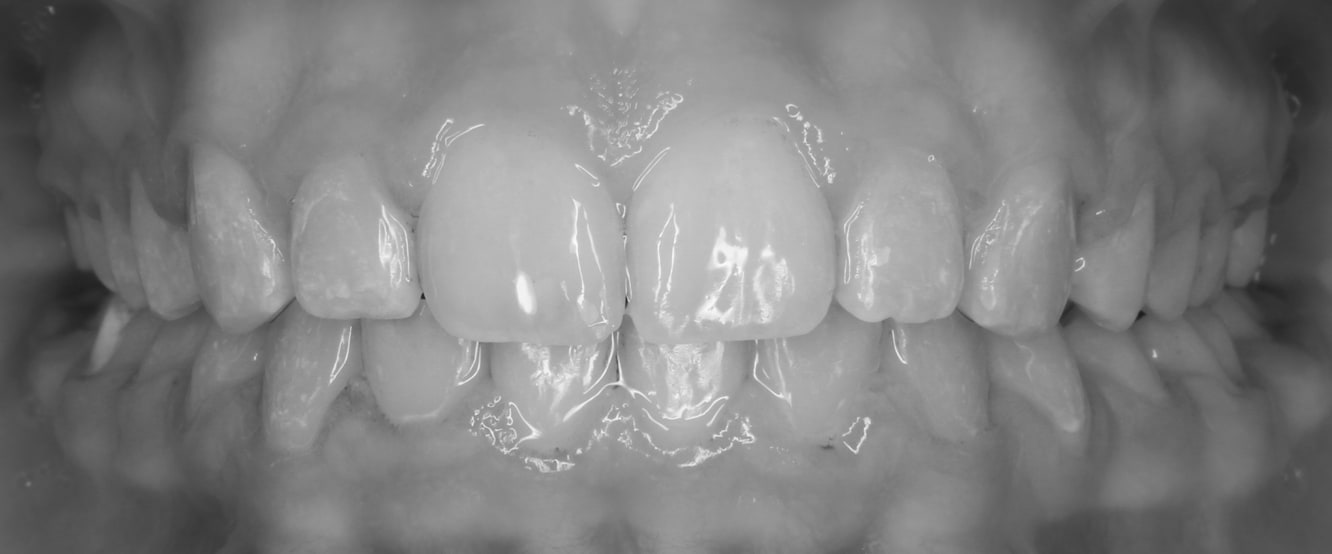

After

Before